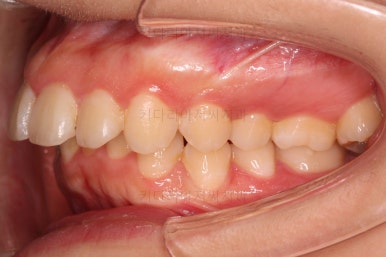

부산무턱교정치과 초진 시 입안의 모습입니다.

전반적으로 치열이 삐뚤고요. 아랫니가 윗니보다 뒤쪽으로 많이 가려져 있죠.

그래서 앞에서 봤을 때 아래 앞니가 거의 보이지 않는 상태인데요.

이런 교합을 "과개교합"이라고 표현합니다.

전반적인 교합, 치열, 과개교합, 튀어나와 보이는 앞니 등을 개선해줘야겠네요.

웃거나 말할 때 튀어나온 앞니가 강조되어 보여 입은 더 나와 보입니다.

아래턱이 작아서 옆모습에서 무턱 느낌이 들고요.

상대적으로 입은 나온 돌출입 양상입니다.